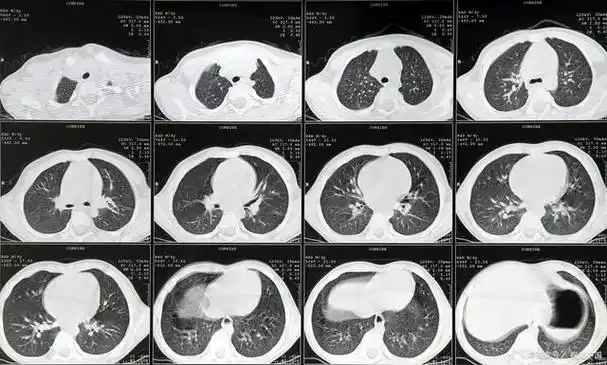

这2种肺结节,极易发展成肺癌!

肺部多发结节首先要考虑是否为转移性肺癌

发现肺结节莫惊慌肺结节肺癌如何复查看这里